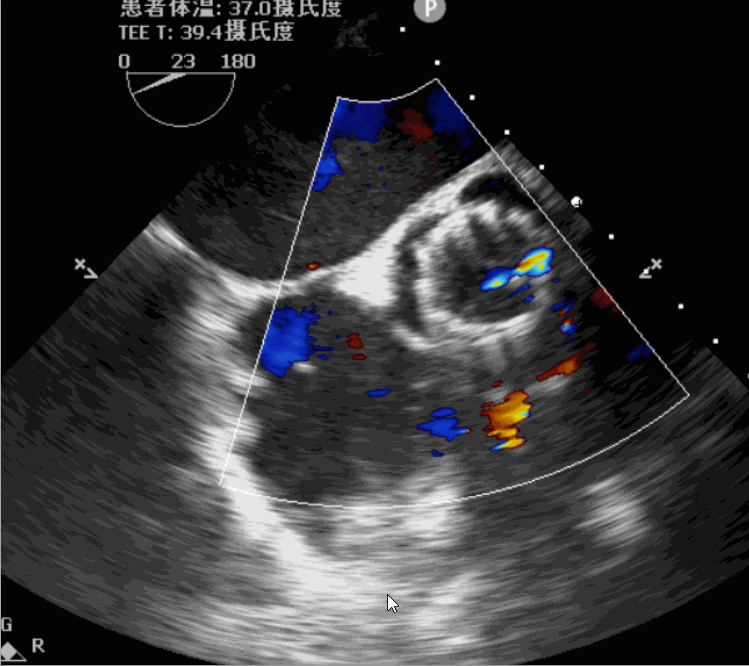

术前超声影像图

术后超声影像图

手术采用左侧心尖处微创手术切口,植入前用25mm球囊进行预扩1次,在DSA及超声引导下植入JS-TAVI 29#牛心包瓣膜,瓣膜释放后造影及TEE确认瓣膜位置及功能良好,采用25mm球囊后扩张1次,手术顺利完成。术前升主动脉根部测压114/41mmHg,左室压154/11mmHg,术后升主动脉根部测压109/50mmHg,左室压94/47mmHg。从导入器械到完成瓣膜置入,耗时8分钟,术中失血30ml,未输血。术后即刻主动脉瓣返流程度由术前大量返流转为消失,术后测得跨瓣峰值流速1.6m/s,平均跨瓣压差4mmHg,峰值跨瓣压差10mmHg。